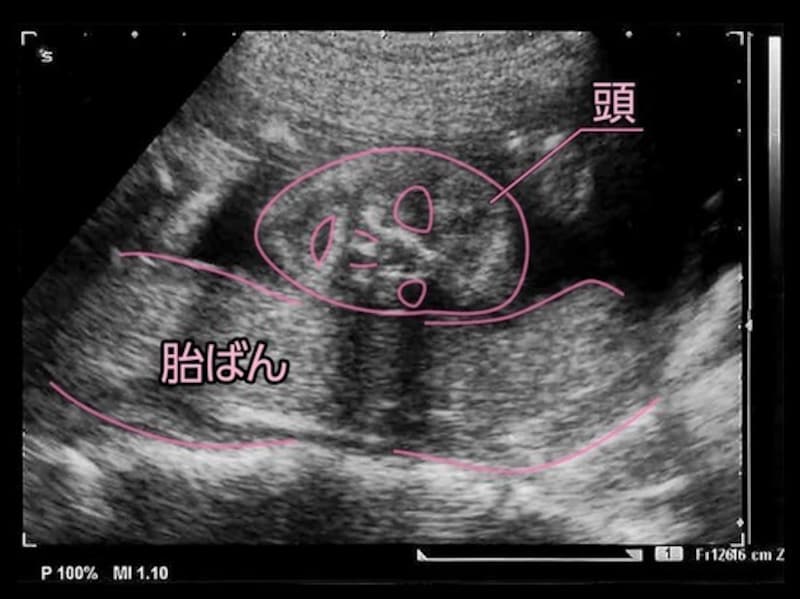

妊娠22週 エコー写真で見る胎児の大きさ・胎動・22週の壁とは

生まれたときにきちんと呼吸ができるように、呼吸器の発達が進んでいきますが、妊娠22週(22w)頃はまだお母さんの胎盤からお臍を通じて酸素が運ばれてきています。内臓や各器官もだいぶ完成に近づき、それぞれの動きが活発になります。